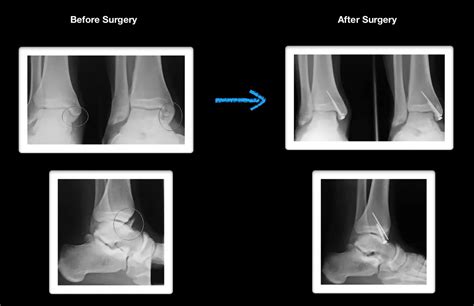

• X-Rays: The primary imaging tool for diagnosing fractures. X-rays can show the location and severity of the fracture.

• Open Reduction and Internal Fixation (ORIF): Involves making an incision to realign the bones and using plates, screws, or rods to hold them in place.